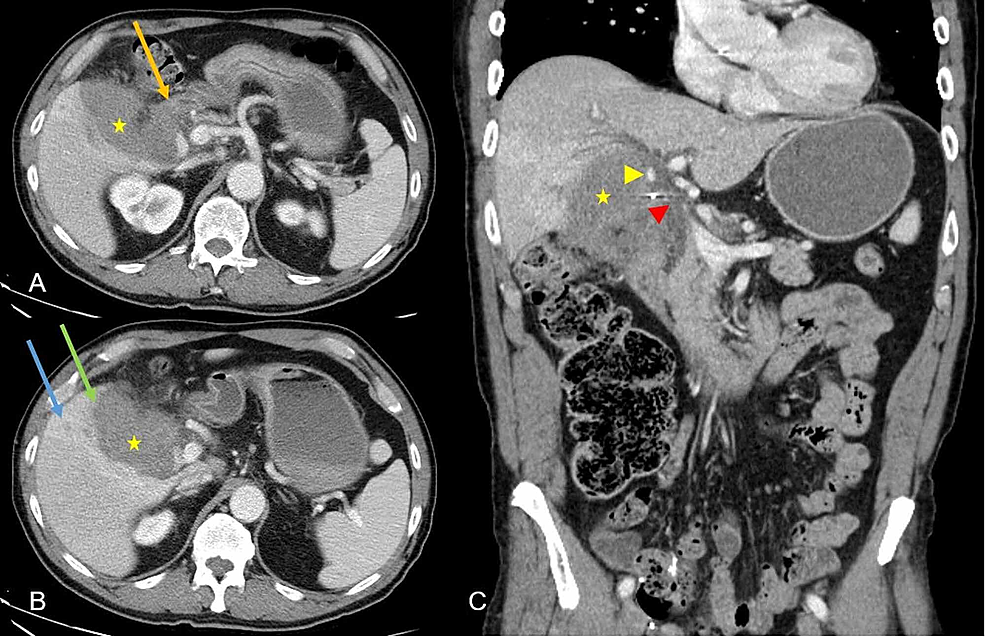

Floating Fetus A Rare Complication Of Balloon Tamponade Treatment

Floating Fetus A Rare Complication Of Balloon Tamponade Treatment

Floating Fetus A Rare Complication Of Balloon Tamponade Treatment